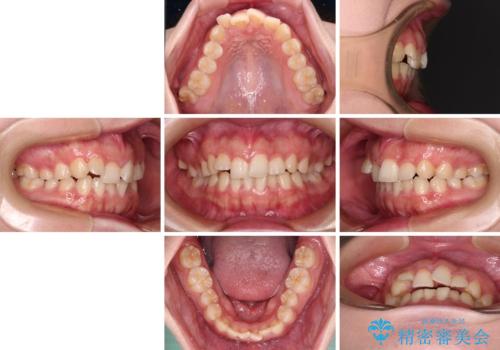

捻れて前に出ている前歯 ワイヤー装置での非抜歯矯正

- 捻れて前に出ている上顎前歯と全体的なデコボコを気にして来院された患者様です。

口元の突出感は強くなかったため非抜歯矯正での対応となりますが、捻転を改善する際に上顎前歯が前突する可能性があったため、上顎臼歯部にアンカースクリューを使用して、歯列が前方に転位しないようにすることとしました。

また舌のトレーニングを行うことで、上顎前歯の突出予防や上下前歯に隙間ができなくなるようにしました。